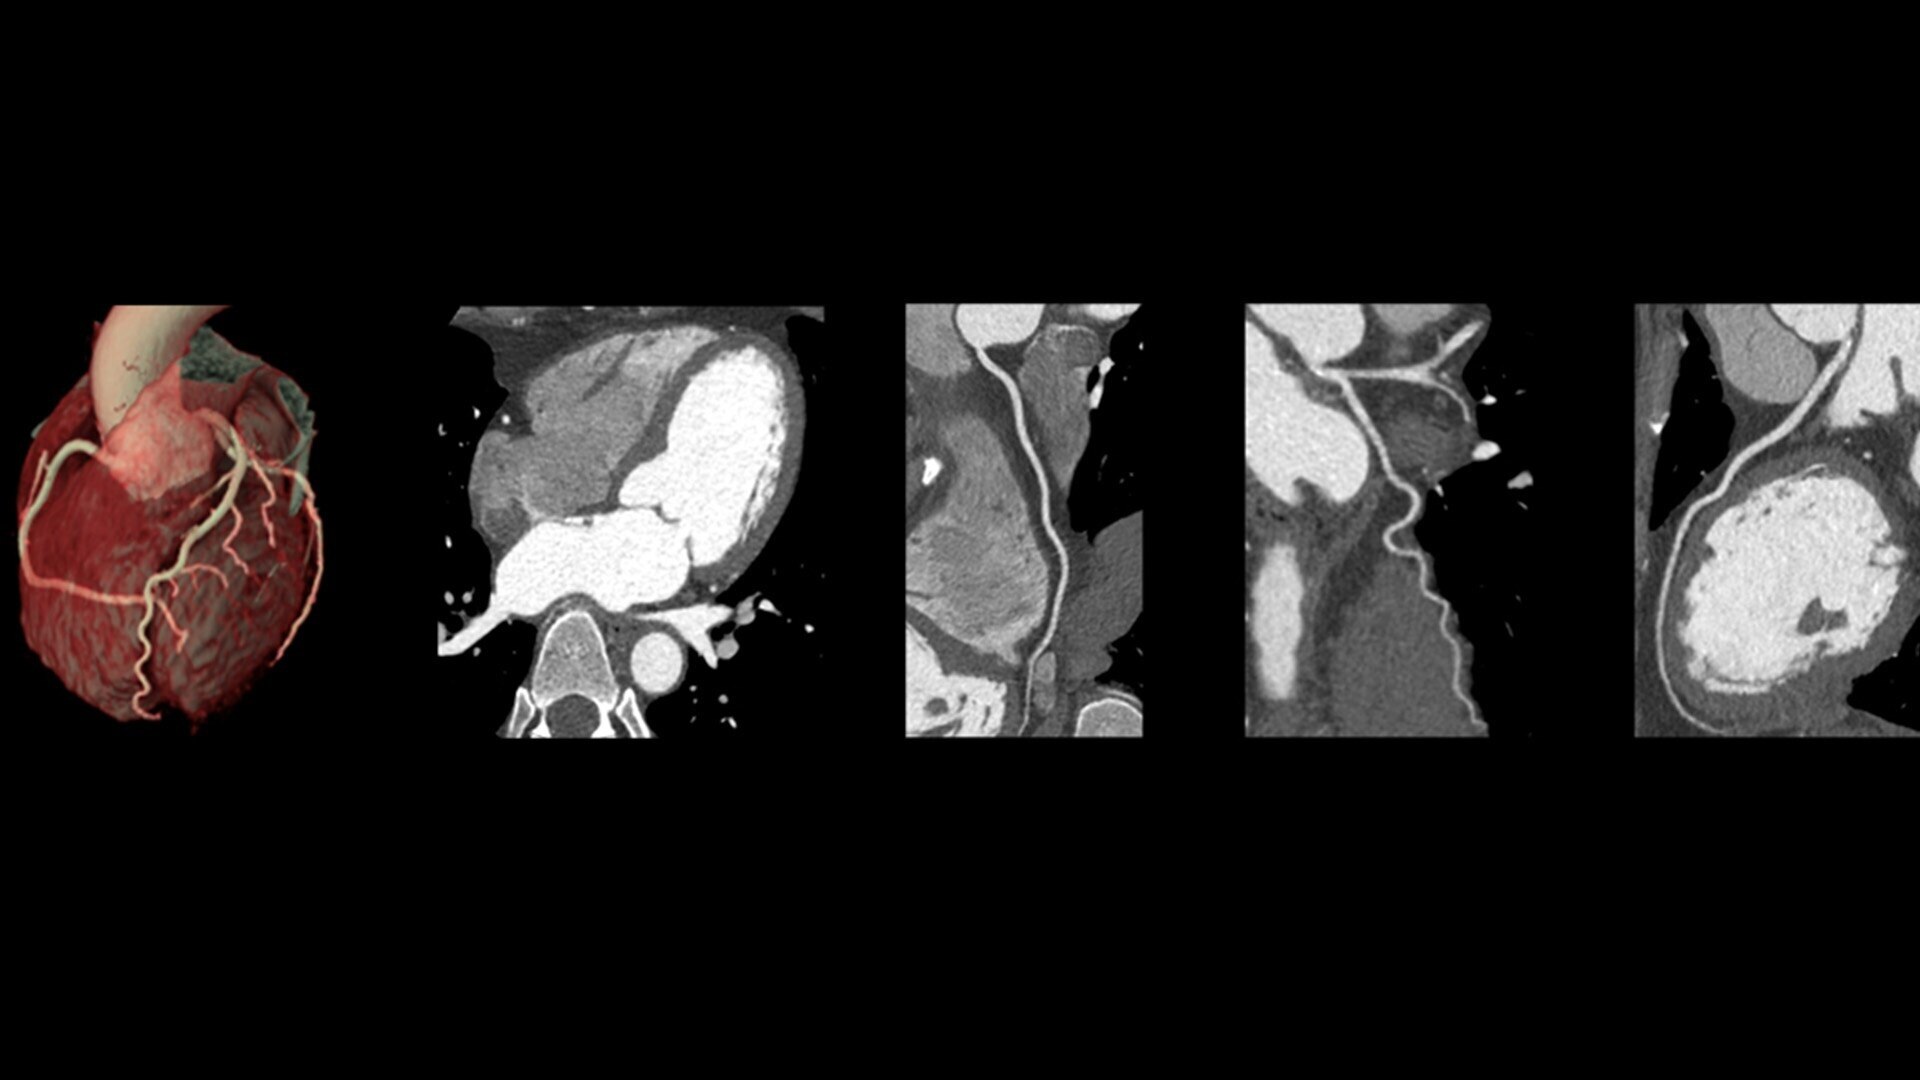

Temporal resolution is a critical factor in cardiac CT imaging because it determines the ability to freeze the motion of the beating heart, thus reducing motion artifacts and improving image clarity. Revolution Apex Elite delivers 19.5 msec effective cardiac temporal resolution, enabling by the fastest 0.23 s gantry rotation and SnapShot Freeze 2 (SSF2) whole-heart motion-correction algorithm.**

ecg-less-cardiac-ct-2-st-en